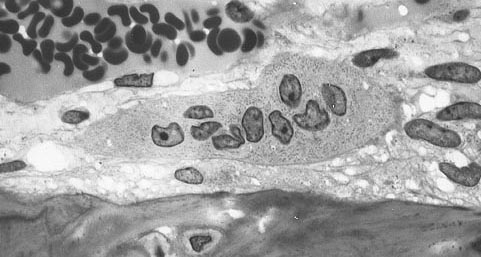

Osteomyelitis is an infection of bone.

Osteomyelitis is most commonly caused by bacteria, and arises via hematogenous spread.

While open-wound bacteremia in adults typically seeds epiphysis, transient bacteremia in infants usually seeds the metaphysis.

Lytic focus is called sequestrum, and sclerosis is called involucrum.

Diagnosis of osteomyelitis is made by blood culture and/or bone biopsy at the site of the lesion.